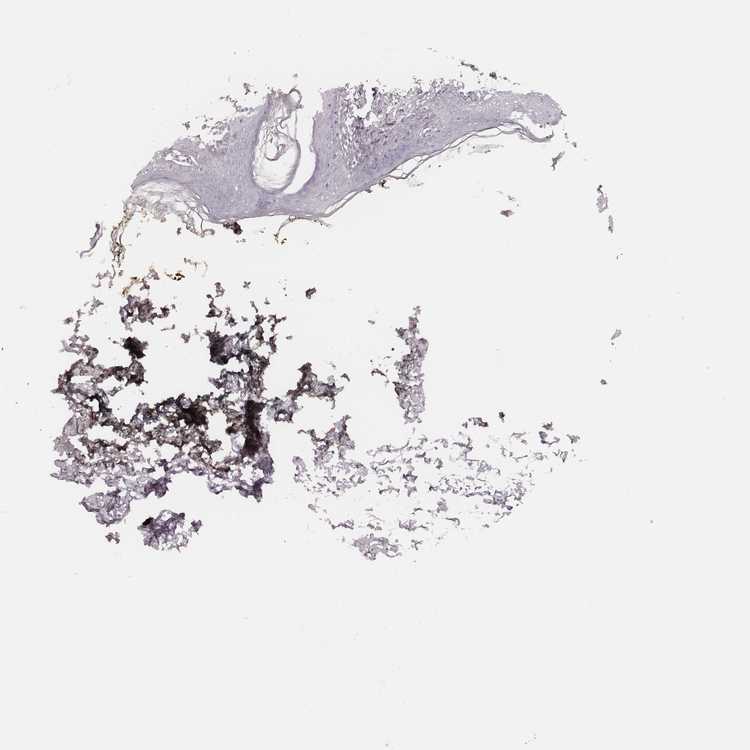

SKIN 1 - Antibody stainingi

Antibody staining in the annotated cell types in the current human tissue is reported as not detected, low, medium, or high, based on conventional immunohistochemistry profiling in selected tissues. This score is based on the combination of the staining intensity and fraction of stained cells.

Each image is clickable and will lead to virtual microscopy that enables deeper exploration of all samples and also displays staining intensity scores, fraction scores and subcellular localization as well as patient and tissue information for each sample.

Antibody HPA065523

Cells in basal layer Not detected

Cells in corneal layer Not detected

Cells in granular layer Not detected

Cells in spinous layer Not detected

Endothelial cells Not detected

Extracellular matrix Not detected

Fibrohistiocytic cells Not detected

Langerhans cells Not detected

Lymphocytes Not detected

Melanocytes Not detected

Vascular mural cells Not detected